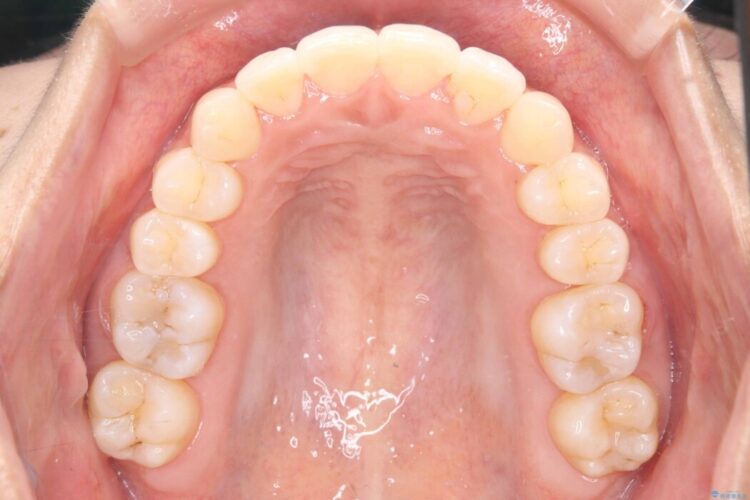

歯の移動量や力のコントロールを最適化することで、短期間で治療完了しました。

「矯正は時間がかかる」というイメージをお持ちの方も多いですが、症例によっては、非抜歯でも短期間で改善が可能な場合があります。

治療後は歯並び・かみ合わせともに大きく改善し、患者様にも大変ご満足いただけました。